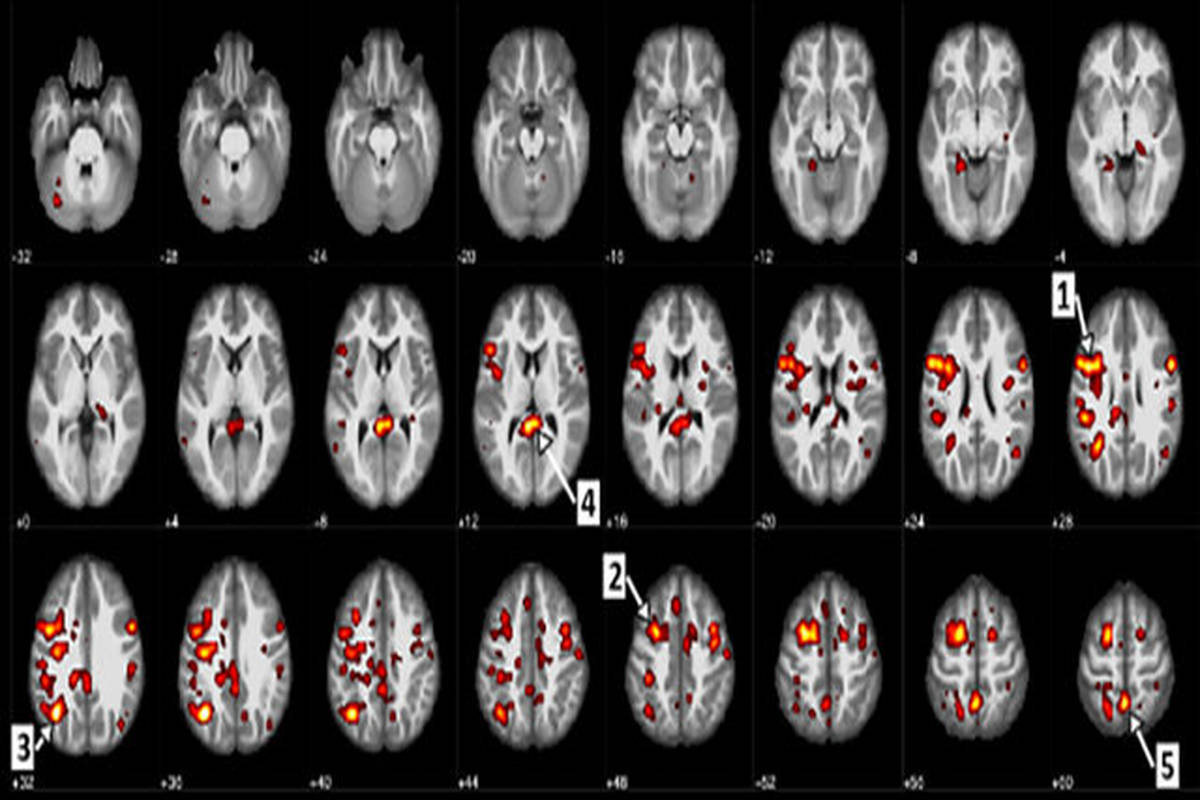

همکاری علمی میان محققان در IBM و دانشگاه آلبرتا در کانادا به ایجاد نرم‌افزاری منجر شده است که می‌تواند اسکن‌های اف‌.ام‌.آر.آی (fMRI) مغز بیماران را تحلیل کرده و با دقت ۷۴ درصدی اسکیزوفرنی را تشخیص دهد.

محققان، ۹۵ اسکن از مجموعه‌ای از بیماران مبتلا به اسکیزوفرنی گرفتند و از آنها به عنوان ورودی اطلاعات در یک الگوریتم یادگیری عمیق استفاده کردند تا با کشف ارتباط میان اسکن‌ها بتوانند درک درستی از اسکیزوفرنی داشته باشند.

آنها سپس از این الگوریتم در برابر اسکن‌هایی استفاده کردند که هم شامل مبتلایان به این بیماری بود و هم افراد سالم را شامل می‌شد.

محققان نشان دادند که این نرم‌افزار قادر به تشخیص سه چهارم اسکن‌های نشان‌دهنده این بیماری است.